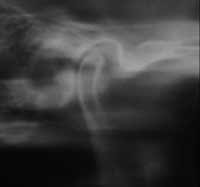

Figure 3 Joint vibration analysis showing stage II anterior disc displacement with reduction.

This patient presented with a Wilkes stage II internal derangement (disc displacement with reduction, Figure 3). Resting and functional EMGs recorded with the Bio-EMG II™ (BioResearch Associates Inc) were used to diagnose how the muscles of the stomatognathic system were functioning with the existing occlusion and also how well they relaxed at rest.14-24 Muscles that function abnormally often do not rest normally either. This can cause pain and tension in the TMD patient. This patient presented with extremely high resting EMGs for the temporalis, masseter, and sternocleidomastoid muscles. This illustrated that the chronic malfunctioning of this patient’s occlusion, along with a chronic history of clenching and forward head posture, was creating a pathological situation that did not allow the muscles to rest adequately. The muscles, joints, and whole body posture were being affected negatively, creating a dwindling spiral that ultimately broke down the whole stomatognathic system and affected this patient’s entire body. The functional EMG recordings indicated the temporalis and masseter muscles had poor left–right symmetry during clenching. This muscle pathology is consistent with poor orthopedic and occlusal schemes where the patient is forced to go through “muscular gymnastics” to facilitate chewing, swallowing, and breathing. The jaw-tracking range of motion and velocity tests (recorded with the JT-3D™, BioResearch Associates Inc) revealed a maximum opening of 41.4 mm. Left lateral excursion was 7 mm, and right lateral excursion was 8 mm. Protrusion was 7 mm. This is considered to be at the low end of a normal range of motion. However, the velocity trace showed an opening speed of only 250 mm/sec and a closing speed of 200 mm/sec, indicating bradykinesia (slow movement). Normal opening and closing speeds should be in excess of 350 mm/second.25-28 A normal opening and closing velocity is consistent with normal muscle and jaw joint function. When there is pathologic opening and closing velocity, there is a potential for muscle and/or TMJ dysfunction.